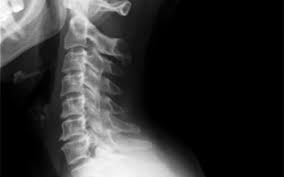

Coluna lombar - perfil em extensÃo mÁxima Paciente Em decúbito lateral ortostático PMS paralelo à LCELCM posicionar de modo que a coluna lombar fique sobre esta linha fazer a extensão ao máximo do paciente forçando ombros e quadris para trás os membros superiores na cabeça ou para atras. Rx de Coluna Inteira. RX Coluna Lombar APPerfilL5S1 Em breve você realizará o exame de RX que visa avaliar ossos e estruturas. Rx de coluna cervical dorsal e lombar para escoliose. Têm uma Smart Fit te esperando agora mesmo. O exame é contraindicado para gestantes salvo em situações nas quais absolutamente. Em casos de RX com contraste poderemos necessitar de punção venosa ou sondagem a depender da indicação e avaliação prévia pela equipe responsável. Não é possível identificar hérnias de disco com esse exame. RX COLUNA DORSO LOMBAR PARA ESCOLIOSE.